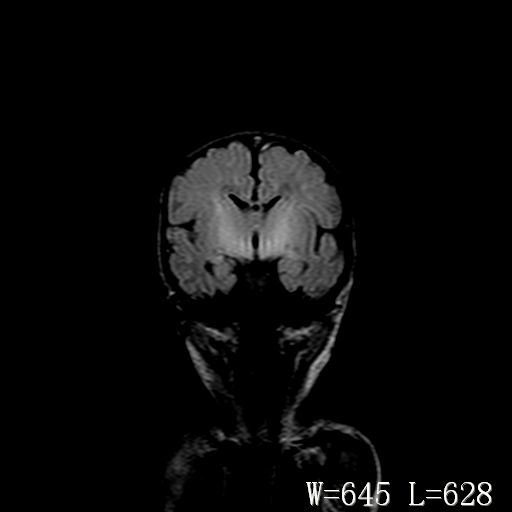

男,4天,发复抽搐1天。

新生儿正常颅脑

hie?

脑干形态欠规则,信号增高,不知怎么解释?

脑干背侧面t1高信号是,新生儿正常已经髓鞘化好的部位